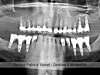

Panoramique de fin des soins 07/2013

Fin des soins 07/2013